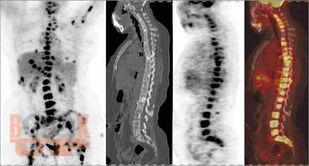

All chapters have been thoroughly revised. The present edition has incorporated 4 new chapters in the musculoskeletal subsections and 2 new chapters in the breast subsection. Content has been divided into 7 different subsections, beginning with current concepts and interventions. The first section deals with all imaging modalities in musculoskeletal imaging. There is an updated section on MR imaging, including new additions of imaging of wrist and ankle; peripheral nerve imaging and imaging of prosthetic joints. The second part of the book contains updated chapters on Breast imaging and interventions and includes two new chapters on Male Breast Imaging and Advances in Breast Imaging. This edition will serve as a concise yet comprehensive guide for students and practitioners of radiodiagnosis as well as a ready reckoner to clinicians in understanding the basics as well as current advances in imaging and interventions.